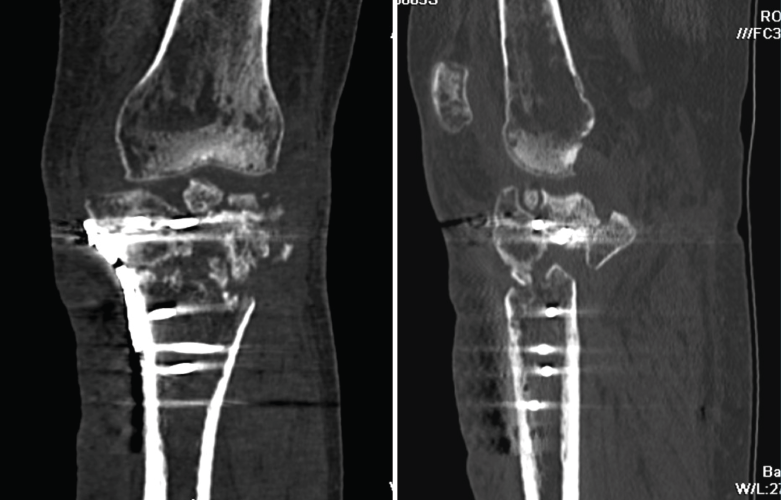

4. Prótesis (Figura 27)

Figura 27. Corte de reconstrucción sagital y coronal de tomografía axial computarizada de rodilla: se valoran los componentes femoral y tibial de la prótesis total.